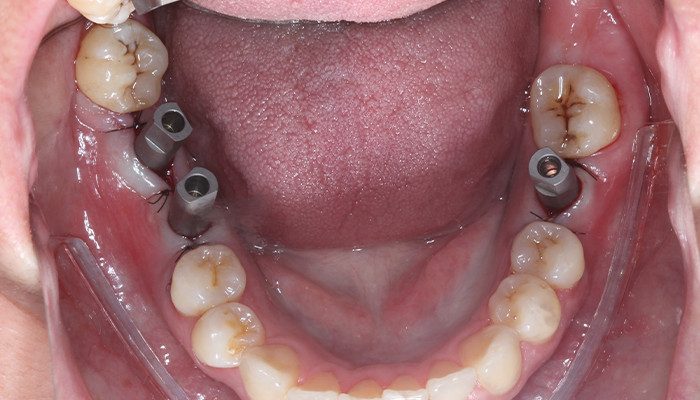

Após instalação e torque de instalação final (32 N.cm para Pilar e 20 N.cm para Mini Pilar) foi suturado e escaneado com Scanner Dexis 3700. Após a primeira impressão digital foi duplicada a malha e apagadas na cópia as regiões dos implantes para aquisição dos scan bodies Aikkon. Em seguida foram removidos os corpos de escaneamento e os intermediários protegidos com coifas de proteção Aikkon e a paciente instruída dos cuidados pós opera tórios e liberada.

15 | Scan bodies Aikkon instalados.